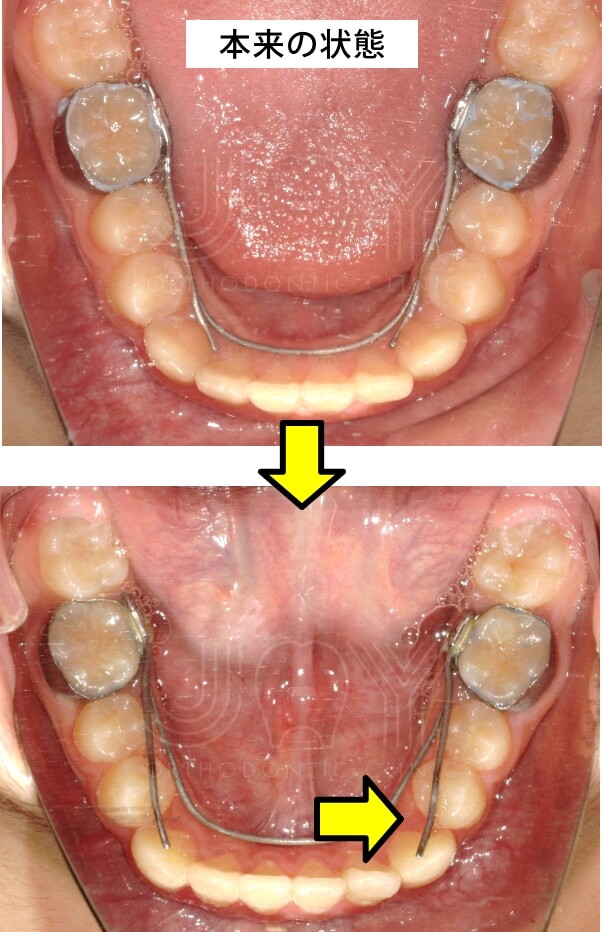

ワイヤーがずれてしまった。

時々、小臼歯を広げている横のワイヤーが下に入り込んでしまうことがあります。

自分で直せるようであれば直して頂いても結構ですが、無理をするとワイヤーが折れますので、ご注意下さい。

当院で調整しますので、ご連絡下さい。

ご自身で直した場合は、その旨を次回診察時にお伝え下さい。 -